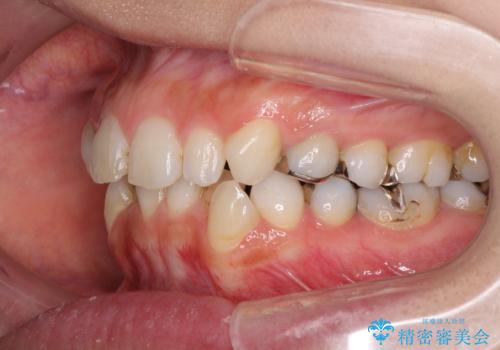

- 前歯のデコボコと矮小歯、更には痛みを感じる奥歯のむし歯を気にして来院された患者様です。

奥歯には根管治療が必要な歯があり、上顎側切歯は左右ともに矮小歯でした。

上下前歯のデコボコはワイヤーでもインビザラインでも対応可能でしたが、補綴治療が多く必要となることから、インビザラインでの矯正治療を行いながら、並行して補綴治療を行うこととしました。

まずは根管治療を行った上で矯正治療用の仮歯を装着し、矯正治療後半に補綴治療を並行して行うこととしました。